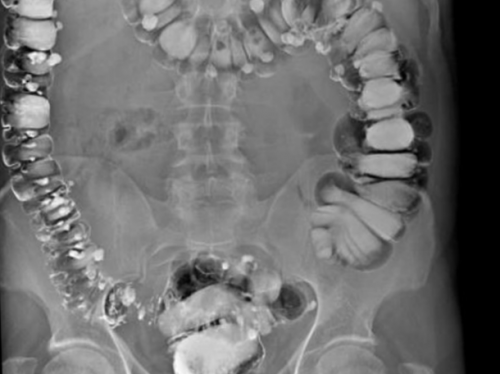

является ирригоскопия, позволяющая достоверно выявить

Ирригоскопия: